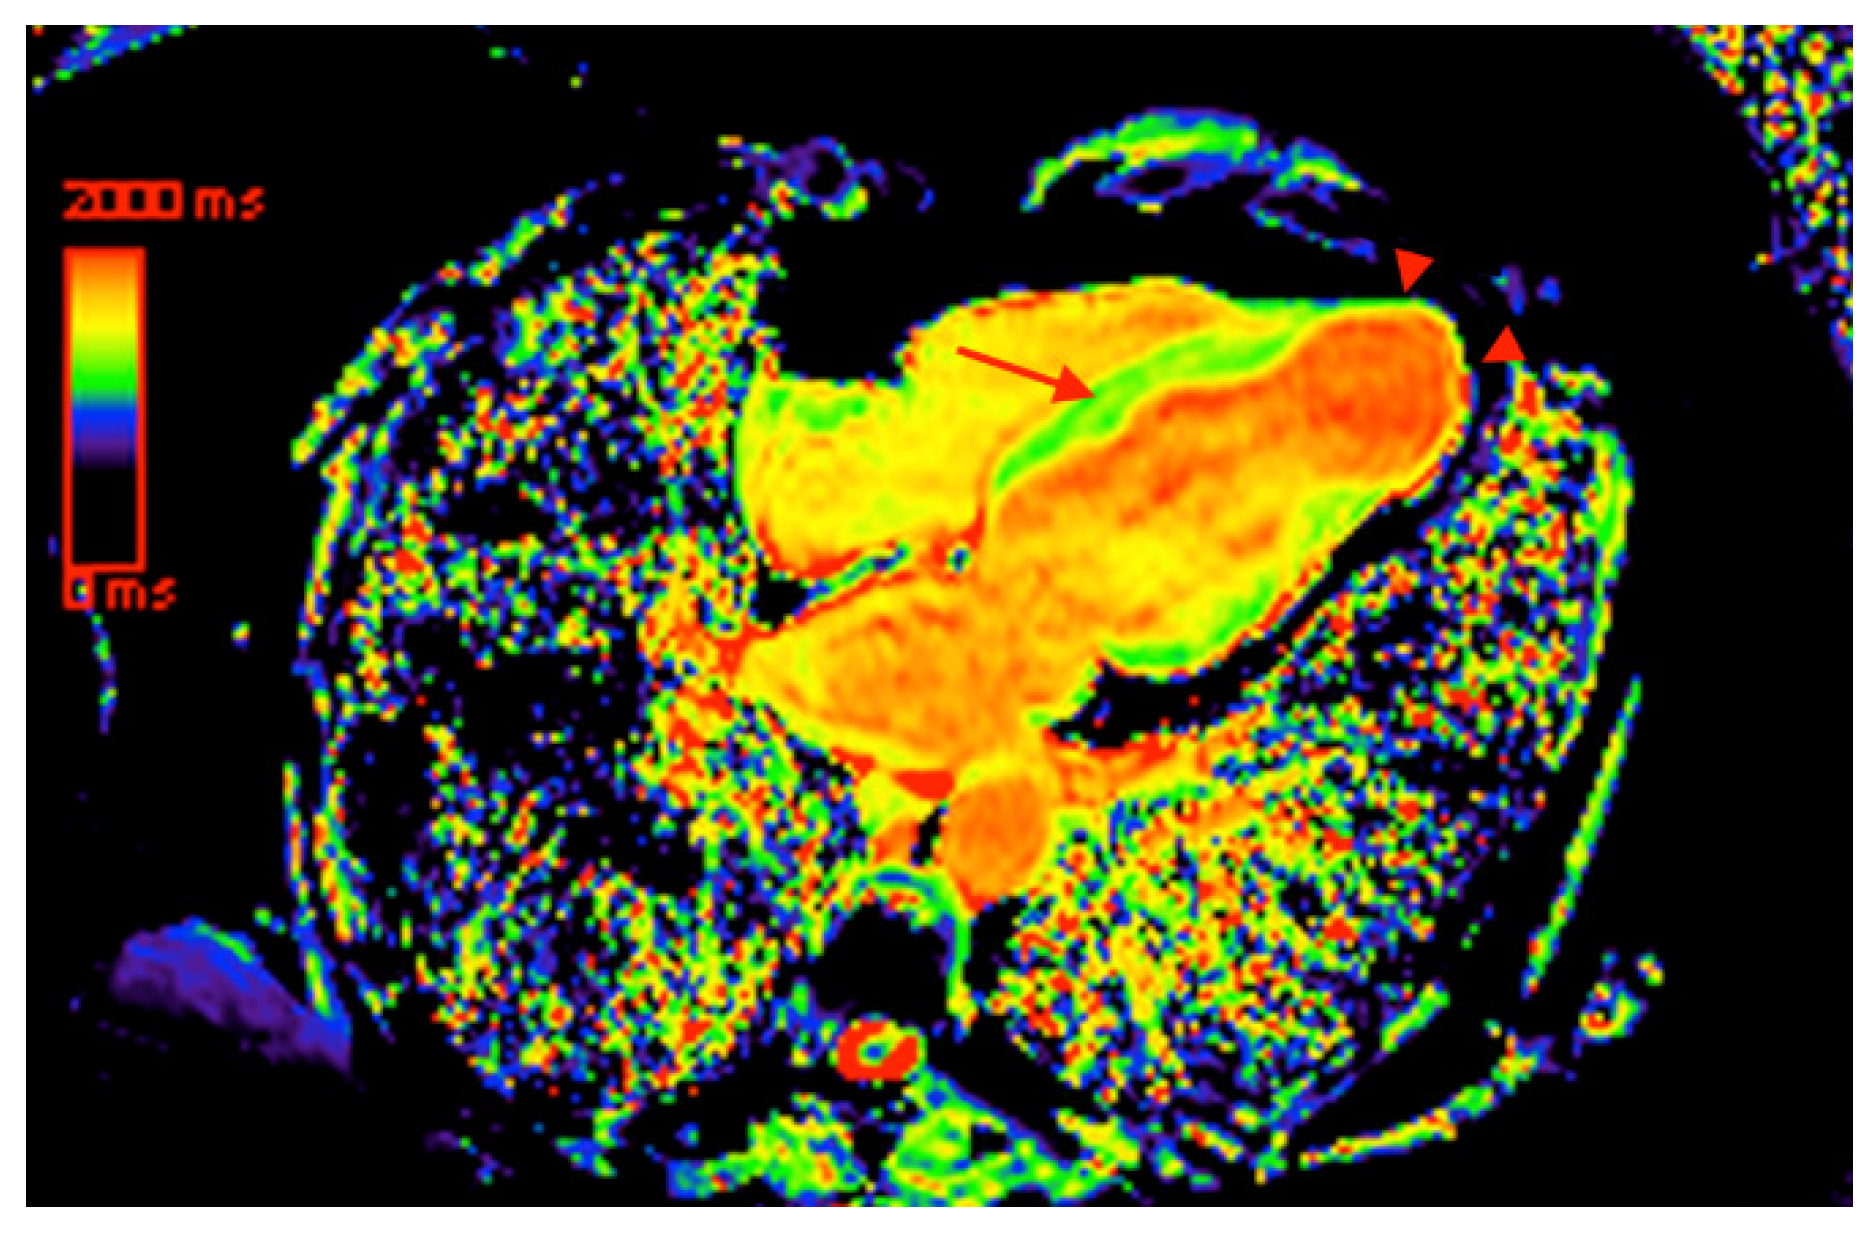

5. Cardiovascular Magnetic Resonance